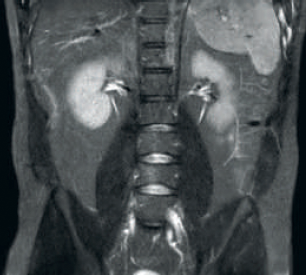

Resultado: SNR e resolução de imagem aprimoradas

Maior consistência e qualidade de imagem aprimorada A tecnologia RF dStream receptora digitaliza o sinal de RM diretamente na bobina de RF, resultando em um aumento da SNR de até 40% ao longo de todo o volume de imagem. Fluxo de trabalho simplificado e produtividade aprimorada A bobina posterior integrada ao tampo da mesa elimina o manejo da bobina em 60% dos exames. A leveza da conformação das bobinas anteriores e as conexões da bobina em um cabo único que pode ser manejado com uma só mão aumentam a facilidade operacional.